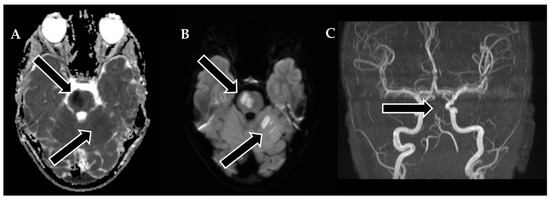

To restore normal blood flow to the affected areas, an aspiration catheter known as “Sofia” (Terumo, Tokyo, Japan) was carefully positioned in the distal V2 segment. Throughout the procedure, multiple left vertebral arteriograms were performed, consistently illustrating blockages in the middle segment of the basilar artery. After six meticulous attempts, a final angiogram conclusively confirmed the complete removal of the obstructions in both the basilar artery and the posterior cerebral arteries, achieving a TICI scale score of 3, indicating full and successful revascularization (Figure 3).

Figure 3. Neurointerventional procedure. (A,B) Initial angiogram from anterior–posterior and lateral views reveals an upper third basilar artery occlusion and no enhancement in both posterior cerebral arteries (TICI scale: 0). (C,D) After the first attempt, angiogram views show improved basilar artery enhancement, but filling defects and absent enhancement persist in both posterior cerebral arteries. (E,F) Post-thrombectomy angiograms demonstrate enhanced perfusion in the basilar artery and both posterior cerebral arteries (TICI scale: 3).